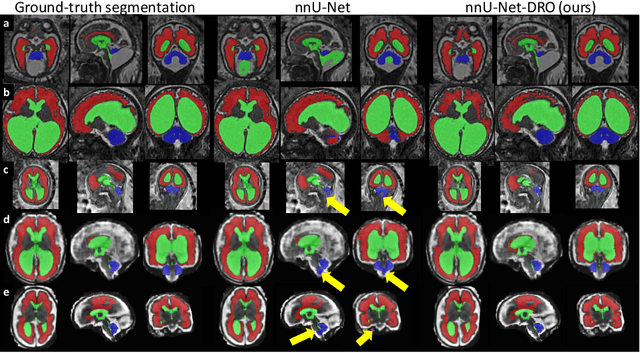

Abstract:The performance of deep neural networks typically increases with the number of training images. However, not all images have the same importance towards improved performance and robustness. In fetal brain MRI, abnormalities exacerbate the variability of the developing brain anatomy compared to non-pathological cases. A small number of abnormal cases, as is typically available in clinical datasets used for training, are unlikely to fairly represent the rich variability of abnormal developing brains. This leads machine learning systems trained by maximizing the average performance to be biased toward non-pathological cases. This problem was recently referred to as hidden stratification. To be suited for clinical use, automatic segmentation methods need to reliably achieve high-quality segmentation outcomes also for pathological cases. In this paper, we show that the state-of-the-art deep learning pipeline nnU-Net has difficulties to generalize to unseen abnormal cases. To mitigate this problem, we propose to train a deep neural network to minimize a percentile of the distribution of per-volume loss over the dataset. We show that this can be achieved by using Distributionally Robust Optimization (DRO). DRO automatically reweights the training samples with lower performance, encouraging nnU-Net to perform more consistently on all cases. We validated our approach using a dataset of 368 fetal brain T2w MRIs, including 124 MRIs of open spina bifida cases and 51 MRIs of cases with other severe abnormalities of brain development.